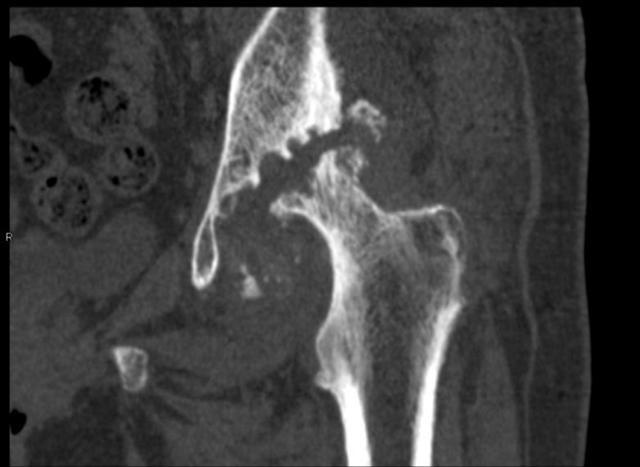

骨頭的空隙處是已經(jīng)消失缺損的髖臼。

70歲的彭阿姨家住漢陽,一周前她因髖部疼痛劇烈,無法行走,被子女送到武漢市第一醫(yī)院骨科住院治療。管床醫(yī)生張麟檢查發(fā)現(xiàn),彭阿姨的左腿比右腿短了3厘米,片子上左側(cè)股骨頭已經(jīng)消失看不見了。

剛開始,她感覺腿舒服了不少,一段時間后疼痛反復(fù)且更加嚴(yán)重,以為是藥量不夠,就加量服用。沒想到現(xiàn)在痛得連路都走不了。彭阿姨最終確診為左側(cè)股骨頭無菌性壞死,髖臼缺損,接受左側(cè)髖關(guān)節(jié)置換術(shù)后,15日康復(fù)出院。